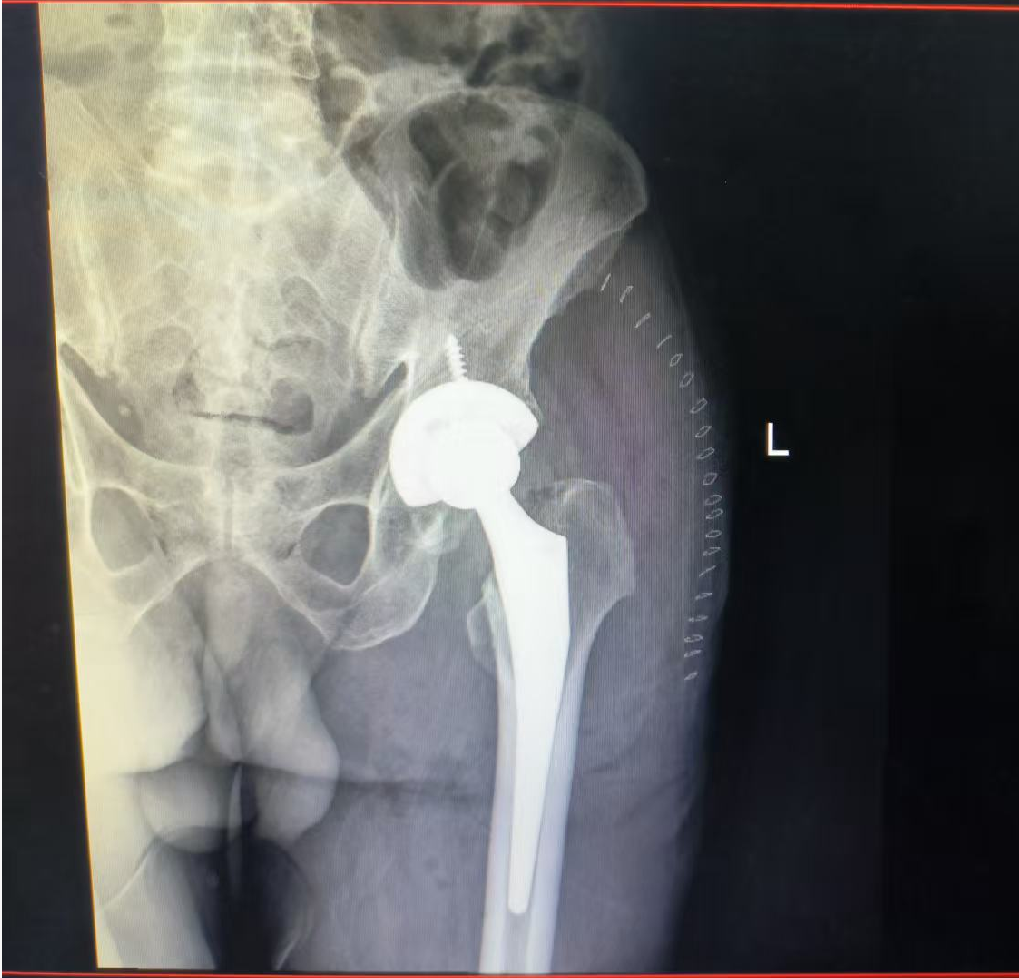

近日,九江市骨科医院骨伤六科(关节骨科)在张平主任的带领下,成功为一位因在家延误治疗、并发多种严重内科疾病的67岁陈旧性股骨颈骨折男性患者,实施了病情复杂的全髋关节置换术。

据经管医生江振介绍,患者骨折超过40天,术前相继出现消化道出血、严重贫血(血红蛋白43g/L)、低蛋白血症(白蛋白25.4g/L)及下肢深静脉血栓,这一系列表现是延误治疗风险的严峻写照。且患者平素患有高尿酸血症(680umol/L)、慢性肾病等。对于60岁以上的人群,股骨颈骨折因其血供特殊,极易导致骨折不愈合和股骨头缺血性坏死,若采取保守治疗(如卧床牵引),患者将面临一系列危及生命的并发症,致死致残率极高。

由于患者术前已发生下肢DVT是关节置换术的“红色警报”,有术中术后血栓脱落导致致死性肺栓塞的风险。团队在术前为患者放置了下腔静脉滤器,为手术筑起了“生命护栏”,这是手术得以安全开展的关键前提。术中,张平和团队凭借丰富的复杂关节置换经验,术中精细操作,克服了组织粘连、骨质条件差等困难,为其成功实施人工全髋关节置换术。目前患者恢复良好,已可借助助行器下地行走。

国际主流观点认为,对老年股骨颈骨折,在身体条件允许的情况下,应积极手术治疗,目的是让患者尽早离床活动,避免并发症,最大限度恢复功能,提高生存质量。手术方式主要包括内固定术与关节置换术。对于高龄患者(通常>65岁)、骨折移位明显、骨质疏松严重或本身已有髋关节疾病的陈旧性骨折,人工全髋关节置换术已成为首选的金标准方案,可一劳永逸地解决疼痛和功能问题,避免二次手术。